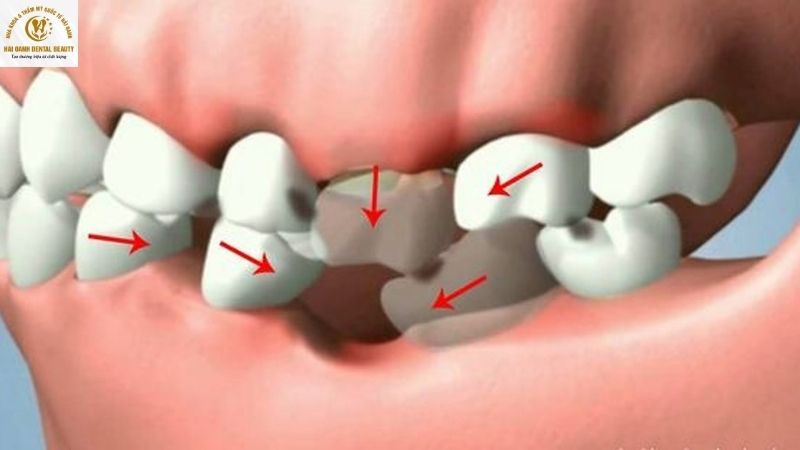

2.3. Răng xô lệch và trồi dài

Khi xương hàm bị tiêu biến, các răng còn lại sẽ mất đi nền móng vững chắc. Các răng này có xu hướng xô lệch, nghiêng đổ vào khoảng trống của chiếc răng đã mất. Đồng thời, răng đối diện trên cung hàm cũng có xu hướng trồi dài ra để tìm kiếm khớp cắn. Điều này dẫn đến sự mất cân bằng khớp cắn, gây khó khăn khi ăn nhai, đau khớp thái dương hàm cũng như làm tăng nguy cơ mất thêm nhiều răng khác.